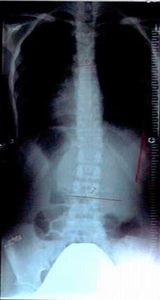

症例14)

信州大学12度→15度進行性、ここから当院通院で体操3ヶ月で6度に改善。

�@12歳 6年生 女子

平成19年6月 12度 信州大学病院 体操指導なし。

平成19年12月 15度 信州大学病院 体操指導なし。

�A平成20年1月27日 大塚整体 初診

側湾症改善大塚式鍛錬体操指導。

�B平成20年3月

6度

に改善正常範囲となる。定期検診は信州大学。

この2ヶ月間で2回体操指導。

レントゲンの比較で15度→6度の改善は明らかで脊柱がほぼ真っ直ぐです。

平成19年6月

経過観察

平成20年3月未検診

初診から体操2ヶ月後

12度

15度

6度 正常範囲